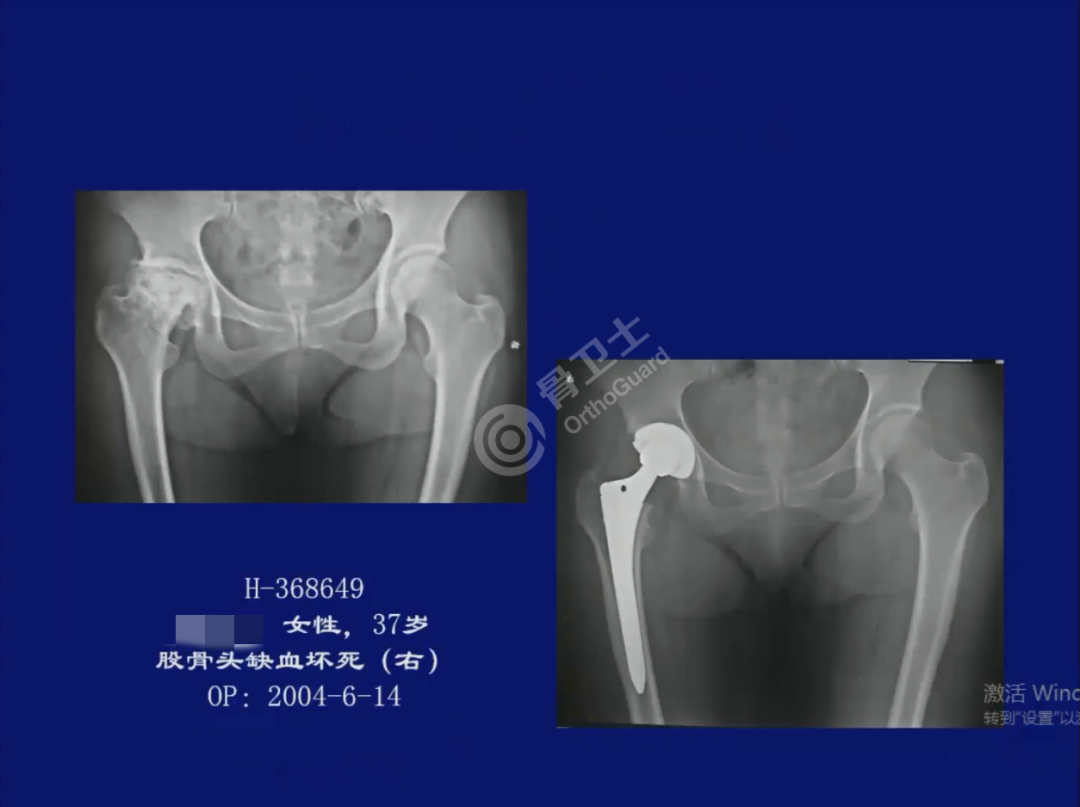

▲解剖正常病例资料